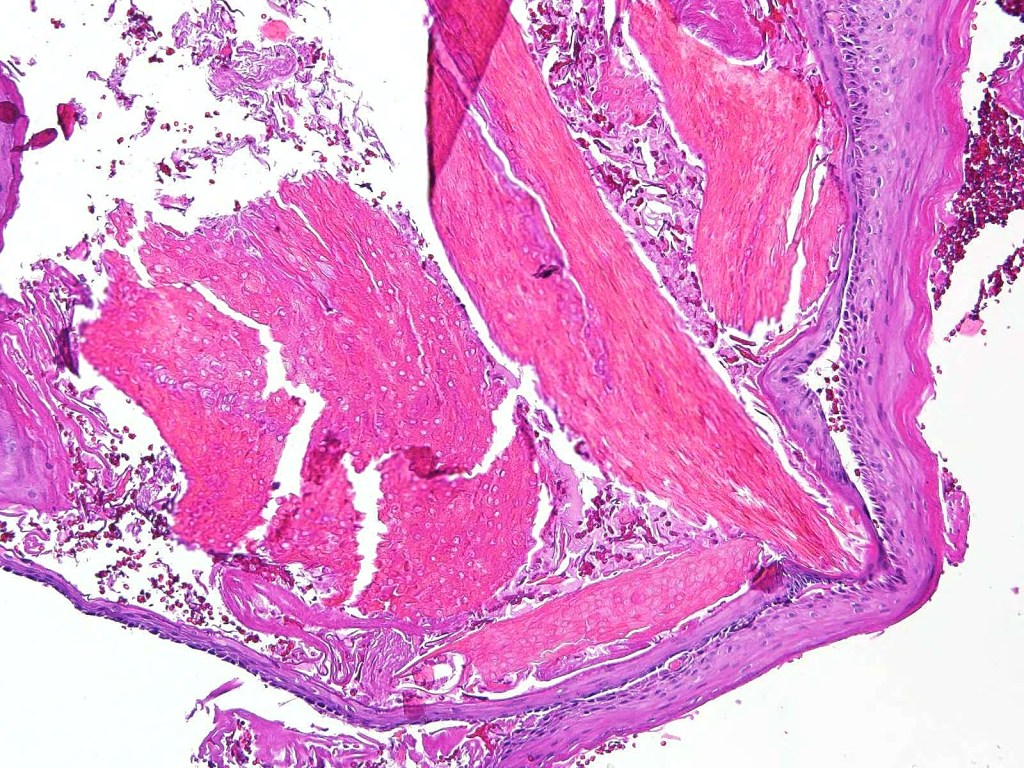

•Well circumscribed unencapsulated, nodular/multinodular silhouette composed of an admixture of epithelial & mesenchymal elements

•Stromal sclerosis & hyalinization

•Myxoid change

•Chondroid foci

•Calcification & osteoid